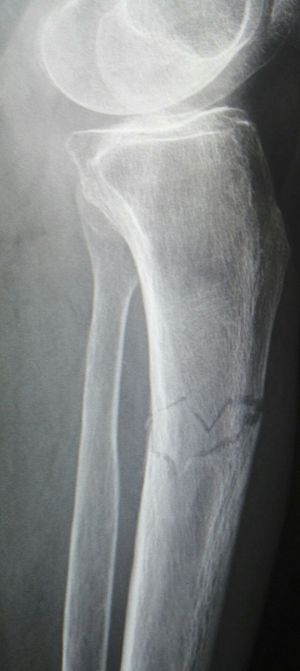

Xray

Fracture

Tibia

Comminuted fracture.